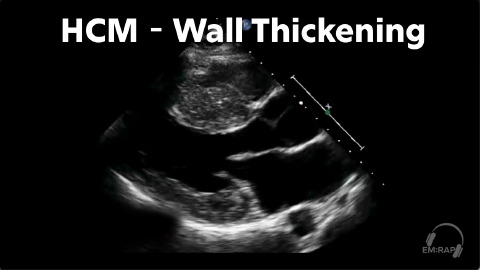

POCUS Diagnosis of Hypertrophic Cardiomyopathy

1 chapterOctober 2024